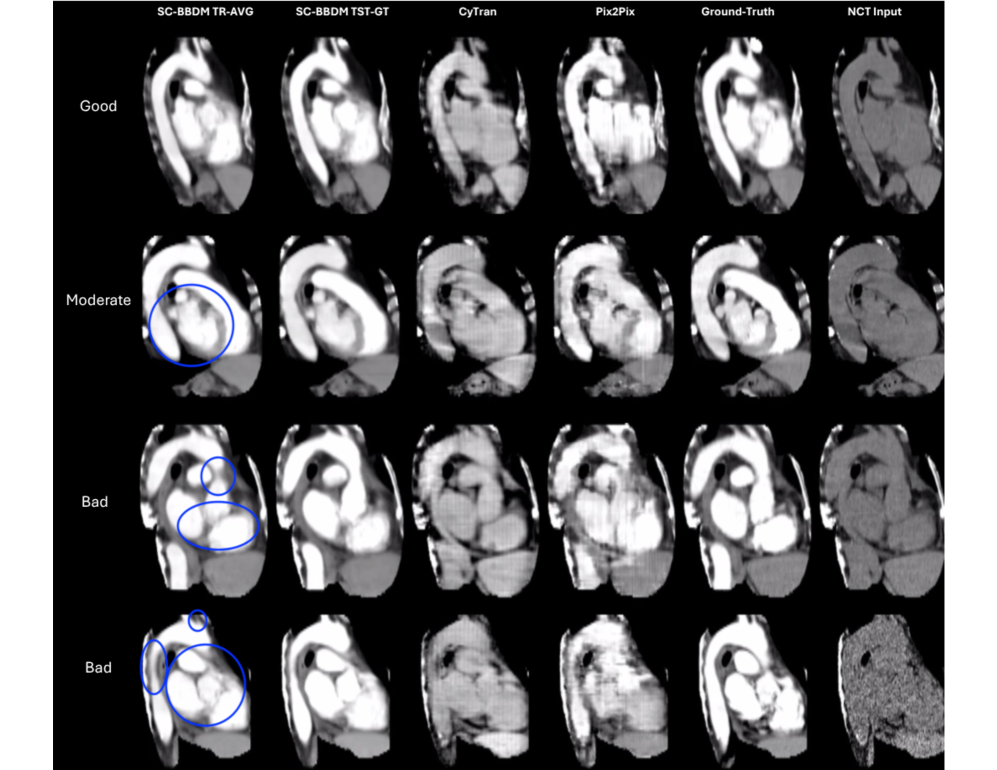

Qualitative results: To gain deeper insight, generated images were reviewed by a radiologist alongside the ground truth. To ensure consistency, we applied appropriate windowing to the ground-truth CTA, input NCT, and generated CTA with a window width of 350 HU and a window level of 50 HU. This adjustment highlights the relevant anatomic structures, allowing for a more accurate assessment of contrast enhancement, particularly in the aorta and heart regions. We have provided videos showing slice-wise performance of SC-BBDM compared to the ground-truth, along with the baselines (CyTran and Pix2Pix), and the input NCT volumes in the Supplementary Material of this paper.

Figure 3 is divided into AV slices (left) and CAV views (right) and groups SC-BBDM’s predictions into three bands: Good, i.e. virtually indistinguishable from the contrast ground truth; moderate, i.e. minor shape or intensity deviations that still leave anatomy recognizable; and bad, i.e. pronounced artifacts that obscure or distort vascular structure. In AV moderate case shows exaggerated fat planes between the main pulmonary trunk and aortic arch (top) and artifactual narrowing of the descending aorta (bottom). Bad cases exhibit blurring of the anatomical borders (as outlined) due to a combination of artifact and hyperenhancement. In CAV, moderate case demonstrates blurring of anatomical borders and loss of cardiac chambers due to hyperenhancement, and bad cases exhibit artifactual narrowing of the aorta and its branches, as well as blurring of cardiac chamber walls. Despite these view‑specific shortcomings, SC-BBDM outputs preserve vessel geometry and intensity distributions more faithfully than CyTran and Pix2Pix, whose images are marred by grid‑pattern texture and streak artefacts.

Refer to caption

Figure 3: Comparison of synthesized images using different methods: the AV dataset on the left side, and the CAV dataset on the right side. Columns represent different approaches. TR-AVG means using the average style key of training, and TST-GT means using the ground-truth style key of test samples. Blue circles highlight notable artifacts or discrepancies.